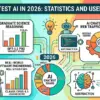

Generative AI achieves over 85% accuracy in predicting mental health treatment success, marking a pivotal shift toward Precision Psychiatry with $10 billion market potential...